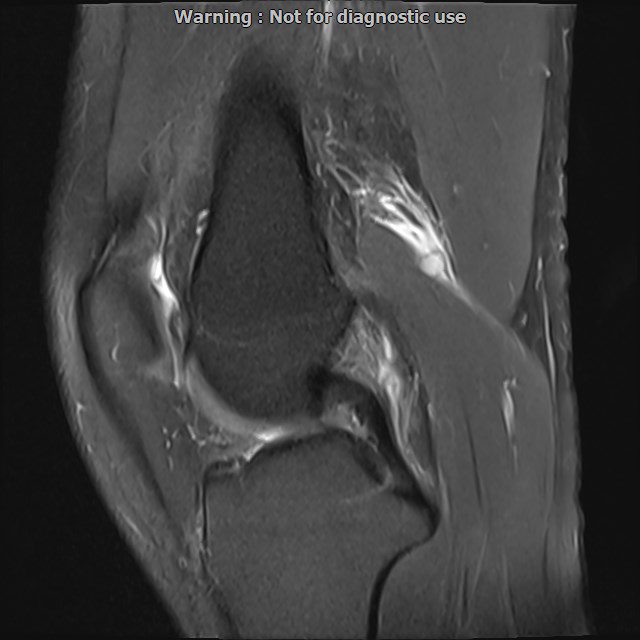

LEFT KNEE MRI

(Without contrast)

Siemens MRI ( magnetom altea 1.5 tesla )

Technique: Sagittal T1, Axial T2 fat sat, coronal & sagittal PD fat sat

– Mild knee joint effusion with soft tissue swelling around the knee

– Low grade partial tearing of ACL with kissing bone bruise in lateral of knee

are seen